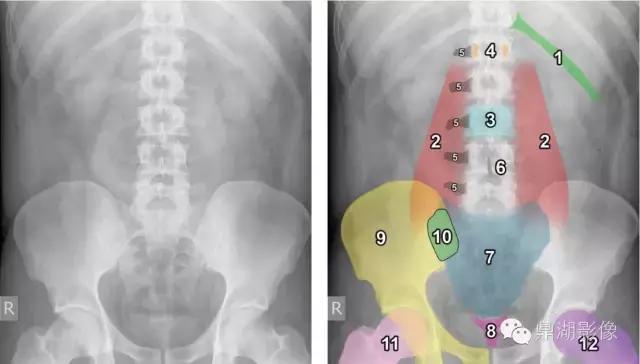

1.左12肋(浅绿色) 2.腰大肌轮廓(红色) 3.L3椎体(浅蓝色) 4.L1椎体(橙色) 5.L1-L5椎体右侧横突(黑色) 6.L4椎体棘突(棕色) 7.骶骨(蓝色) 8.尾骨(玫瑰色) 9.半个骨盆(黄色) 10.骶髂关节(绿色) 11.右股骨(粉色) 12.左股骨(紫色)

1.髂骨(绿色) 2.耻骨(红色) 3.坐骨(黄色) 4.闭孔(紫色) 5.右腹股沟韧带的位置(蓝色)。腹股沟韧带运行髂前上棘和耻骨之间结节 6.Shenton’s线(黑色轮廓)